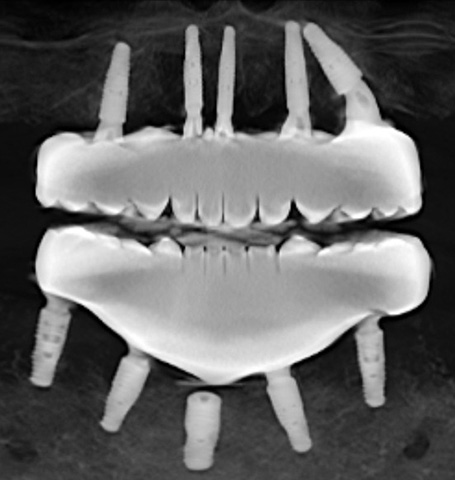

There are several issues with all of the implants, from problems with their locations, problems with mismatched heights from one implant to another, problems with their depth requiring gum grafts as there is no attached gingiva, problems with two of the upper implants apparently touching each other per periodontist report, a few other issues, and all seem to have some level of bone loss around the implants.

All the experts also agreed that the teeth need to be replaced because of the excessive heights and extreme mismatch of the chewing surfaces. Regardless, the teeth need to be redone because implants will be replaced and the screw hole locations will change.

As illustrated earlier in this post, the teeth do not match up which makes it utterly impossible to chew properly. Because they are zirconia, they can not be ground down or modified to enable me to chew even slightly better. Even the slightest amount of grinding will fracture the zirconia.

Also the teeth on each arch are too tall by over 4mm. The teeth hit all the time when I try to talk. The heights of the teeth need to be reduced by at least 4mm on each arch. So we're looking at teeth that are too tall inside my mouth by at least 8mm total. 8mm is 5/16" of an inch. This excessive height also interferes with chewing.

I complained about the size of the teeth on the first temporary set, Bansal insisted they needed to be that size. Then I complained again when Bansal made the teeth even bigger on the last set of temporary teeth, but Bansal insisted the teeth needed to be that size. Some of the dental experts said Bansal must have made the teeth taller to compensate for the other mistakes he made, it's a common trick done by unscrupulous and unprofessional dentists.